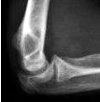

Рентгенография локтевого сустава

Рентгенограмма локтевого сустава в травматологии показана при подозрении на переломы околосуставного и внутрисуставного суставов и переломы плечевой, лучевой и локтевой костей. В других областях медицины этот метод используется для диагностики дегенеративно-дистрофических изменений, новообразований, аномалий развития и гнойных воспалительных процессов. Исследование обычно проводится в два, реже - по прогнозам, оно не требует подготовки. В связи со значительным воздействием излучения оно не проводится детям и беременным женщинам (за исключением неотложных патологий и случаев недоступности альтернативных методов).

В травматологии рентгенограмма локтевого сустава назначается при подозрении на надмыщелковый перелом или перелом плеча, изолированные переломы мыщелка, трансдондилярное плечо, перелом локтя и процесс перелома короноидной локтевой кости шеи и головки лучевого перелома Монтеджи (перелом верхней трети локтевой кости в сочетании с вывих головки луча) и вывих костей предплечья. В гнойной хирургии в качестве показаний рассматриваются ортопедия, онкология и ревматология, гнойный артрит, артроз, пороки развития, ревматические заболевания с поражением локтевого сустава, доброкачественные и злокачественные новообразования.